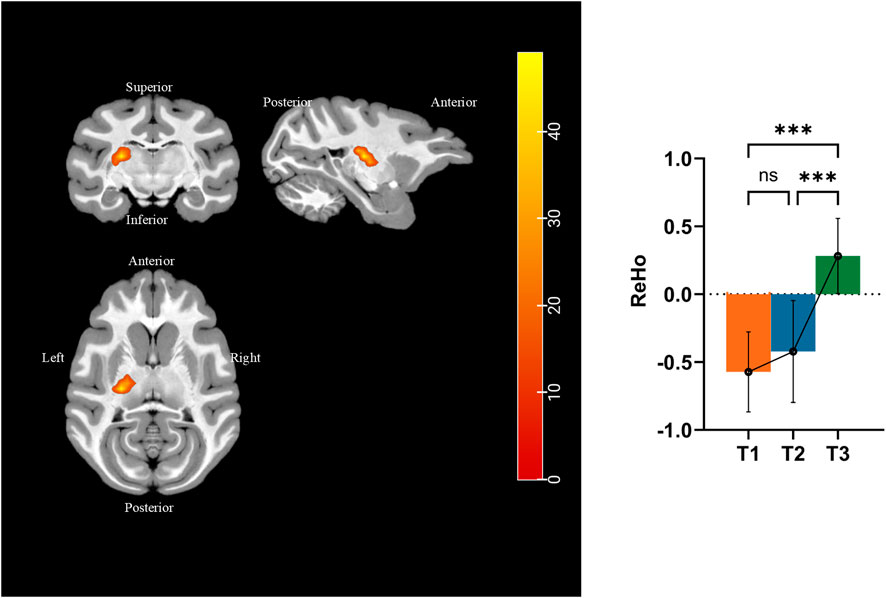

We performed ReHo analysis to identify the functional changes that occurred during simulated microgravity. Results were displayed in the T1 template from D99 rhesus atlas (Goldman-Rakic and Rakic, 1991). Figure 7 and Table 4 show that ReHo in the left thalamic reticular nucleus (RN) underwent significant changes. Compared to pre-HDBR, ReHo in the left thalamic reticular nucleus increased at 21 days of simulated microgravity and continued to increase by 42 days.

Figure 7. Different brain areas in ReHo among pre-HDBR and 21 and 42 days post-HDBR and post hoc analysis. ***, P < 0.001; ns, no significant; T1, pre-HDBR; T2, 21 days of HDBR; T3, 42 days of HDBR. (A) Group difference in FA (T2 < T1). (B) Group difference in MD (T2 < T1). (C) Group difference in AD (T2 < T1). (D) Group difference in RD (T2 < T1).

4.3 Resting-state functional activity change

The fMRI results of this study revealed that simulated microgravity induces an increase in ReHo in the left RN of the thalamus. ReHo measures the temporal synchronization of BOLD signal fluctuations among neighboring voxels within a brain region, and the standardized ReHo reflects enhanced local functional synchronization, suggesting heightened neural activity or improved coordination in the region. Compared to pre-HDBR baseline levels, HDBR caused significant changes in ReHo values in the left RN region, with these changes continuing over prolonged HDBR exposure. RN is a thin layer of gray matter located between the lateral thalamic nuclei and the internal capsule. RN suppresses thalamic excitatory neurons via GABA release, thereby serving as a gatekeeper to regulate rhythmic activity in the thalamus and cortex. This inhibitory control enables the RN to modulate thalamus-related behavioral processes, particularly attention regulation, sleep–wake cycles (Barthó et al., 2014), and social memory (Feidi et al., 2024). Similar to a previous 72-h HDBR study (Liao et al., 2012), the thalamus has been recognized as a key target for neural alterations under microgravity. In our study, the enhanced local synchronization in the RN may reflect compensatory upregulation of inhibitory control within thalamus-related neural circuits under simulated microgravity. This could represent an adaptive mechanism to counteract disrupted sensory–motor integration or altered thalamocortical dynamics in a gravity-deprived environment.